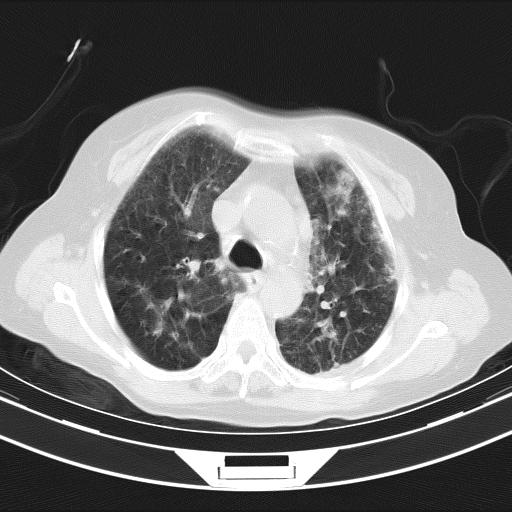

老年女性,嗜睡3天,意识模糊。轻咳,无发热。

双肺多发淡片影,毛玻璃影,,支持支气管肺炎,,建议血气找原因,,嗜睡是否肺性脑病?有没有慢支病史?

1)两肺感染性病变;建议抗炎治疗后复查。2)纵隔淋巴结肿大。3)左侧胸腔积液。

1)先考虑两肺感染性病变;建议抗炎治疗后复查。

2)纵隔淋巴结肿大。

3)左侧胸腔积液。